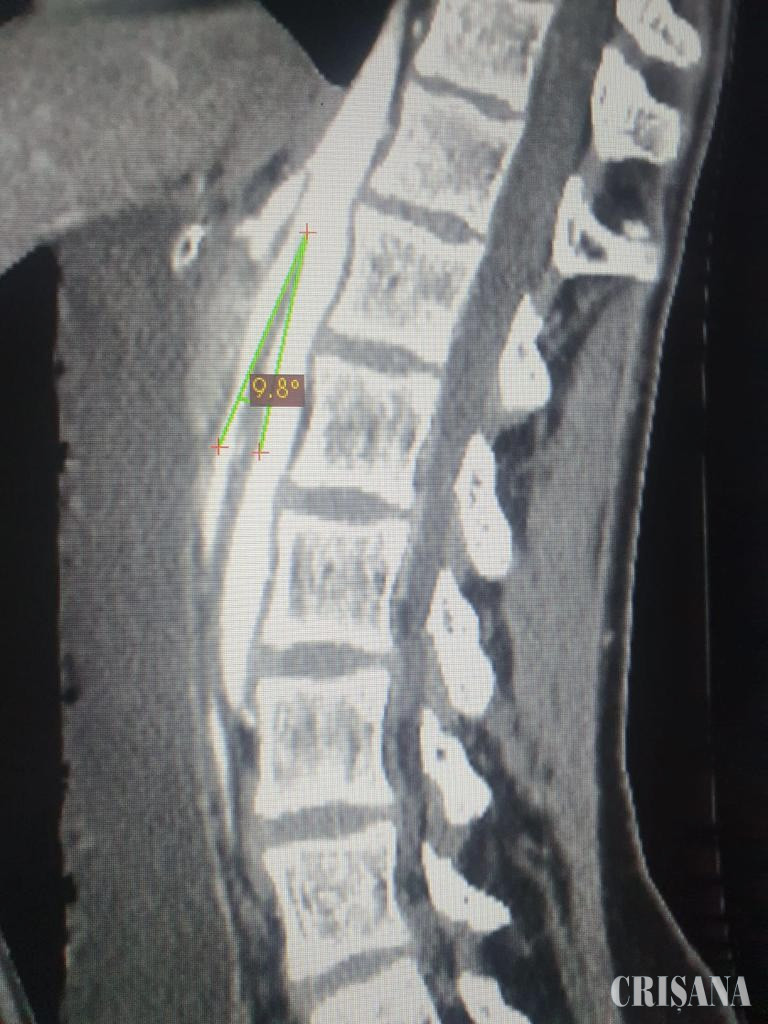

Aceste simptome indicau prezența unei obstrucții proximale, așadar inițial, pacientei i s-a efectuat o radiografie abdominală. S-a constatat faptul că stomacul pacientei era destins până la micul bazin, în mod normal acesta fiind situat până deasupra ombilicului. De asemenea, evacuarea era încetinită. Așadar, pacientei i s-a făcut tomografie computerizată a abdomenului cu substanță de contrast intravenoasă și a fost măsurat unghiul aorto-mezenteric, adică unghiul dintre aorta abdominală și artera mezenterică superioară. Acest unghi trebuie să fie de peste 25 de grade, pentru a permite trecerea duodenului (prima parte a intestinului subțire). În cazul pacientei, unghiul era de doar 10 grade, ceea ce a dus la comprimarea duodenului și astfel, la apariția simptomelor pacientei.

În urma acestor investigații, s-a pus diagnosticul de sindrom de pensă aorto-mezenterică. Această afecțiune este o cauză extrem de rară de obstrucție intestinală. Punerea diagnosticului a presupus o abordare multidisciplinară a cazului, necesitând analize de laborator, împreună cu investigații de imagistică medicală și gastroenterologie. Sindromul de pensă aorto-mezenterică are o incidență de 1 la 1 milion în rândul copiilor (0-18 ani), iar acesta este primul caz înregistrat în județul Bihor și al doilea caz publicat din țară. Atât diagnosticarea acestui caz, cât și abordarea chirurgicală reprezintă premiere medicale la nivelul județului Bihor.